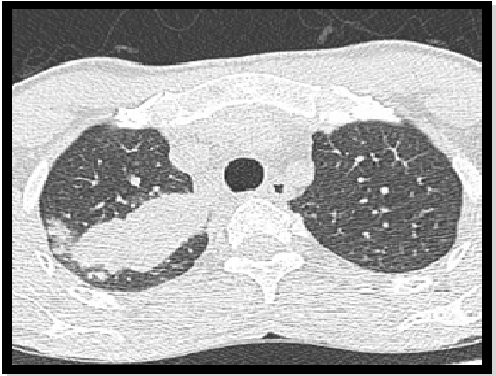

胸部X光片和CT扫描显示(图:1,2,3,4,5,6,7):

1、肺部空腔,包含坚实的圆形物质,通过空气边缘与墙壁分开。此功能称为“空气新月”标志。

2、另一个常见特征是腔壁和邻近胸膜增厚。

3、这种真菌球可能是移动的。

图1:腐生性曲霉菌。肺窗的仰卧MDCT扫描显示重力依赖性腔内肿块。

图2:腐生性曲霉菌。图1患者的俯卧MDCT扫描,肺窗显示重力依赖性腔内肿块。